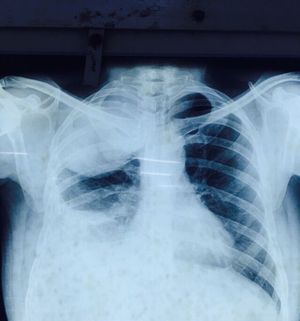

43yr old Male Mr.Kiran , Non-Hypertensive and Non-Diabetic has come with the complaints Breathlessness for 2months, Mild to moderate chest pain for 3 weeks, Fatigue for 2weeks and Fever on&off for 4 days. X ray PA view was taken prior to Other investigations. Give me at least 3 Differential Diagnosis for this case.

Pneumococcal pneumonia; bronchial carcinoma; abscess formation in lung